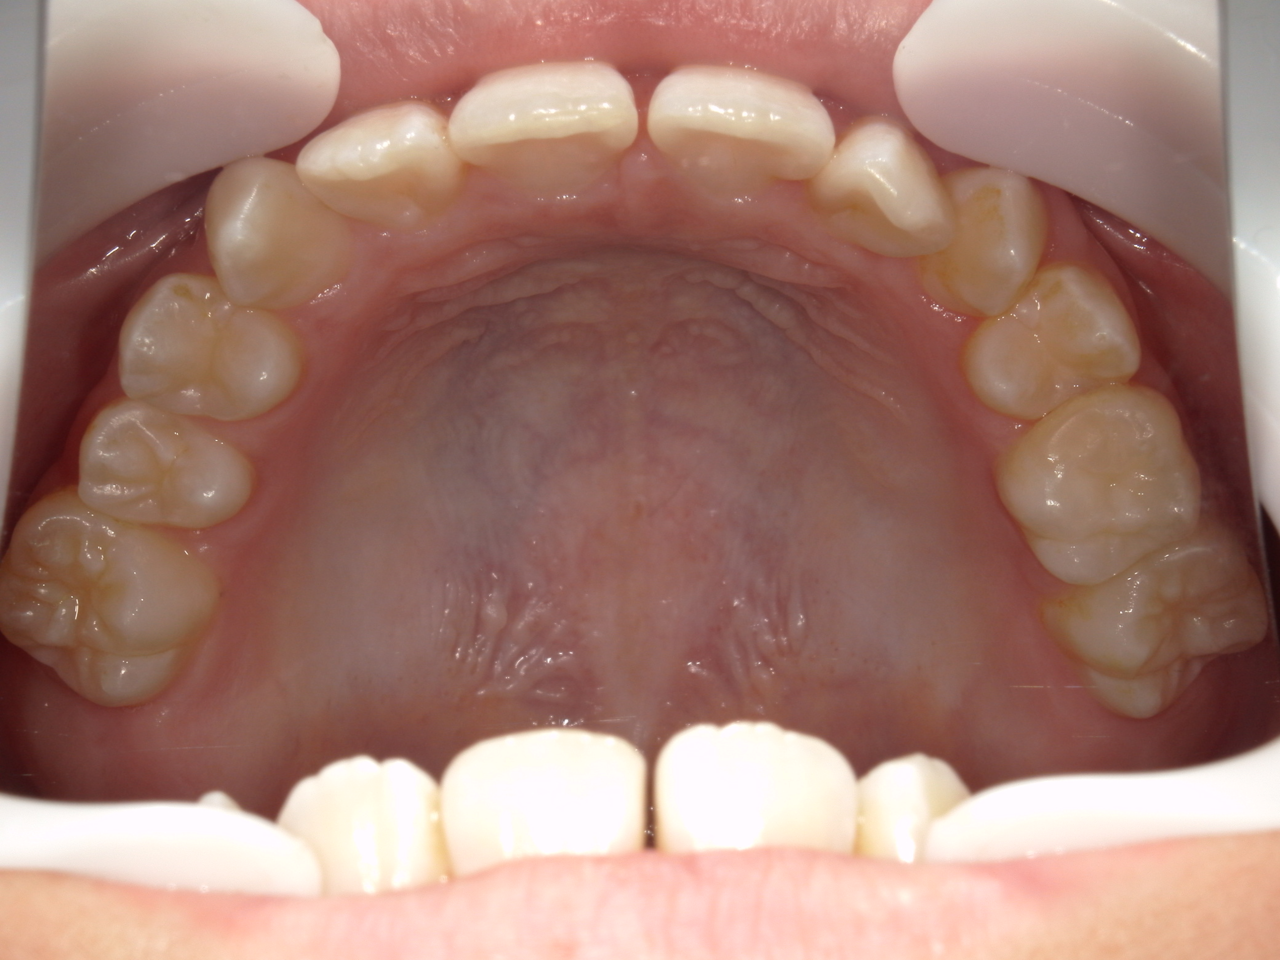

治療前

治療説明 歯科矯正で取り外し可能な矯正方法である床矯正で治療しました

治療期間 4年

治療費用200000 円

治療後

治療の副作用(リスク)歯の動き方には個人差があり、予想された治療期間が延長する可能性があります。。床矯正の使用状況、矯正歯科治療には患者さんの協力が必要であり、それらが治療結果や治療期間に影響します2次矯正が必要になる場合もあります。